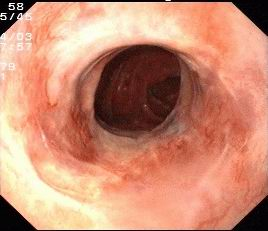

⑥ERCP

内镜下逆行胰胆管造影术(ERCP)指在内镜下经十二指肠乳头插管注入造影剂,做胆胰管X线造影胆汁细菌学和细胞学、胆道压力及乳头括约肌功能测定等检查,是公认的诊断胰胆管疾病的金标准。在ERCP的基础上可作十二指肠乳头括约肌切开术 、胆胰管碎石取石术 、胆胰管内支架安置引流术 、 鼻胆引流术及胆道蛔虫取出术等治疗。我院消化内科开展ERCP、EST等内镜 微创技术多年,至今已经完成多例胆道结石、蛔 虫、肿瘤、先天异常等疾病的的内镜诊疗,取得很好效果。

ERCP提示胆总管结石

切开乳头

取出结石

支架引流术

【内镜下十二指肠乳头括约肌切开取石术(EST)】

胆总管结石可引起急性化脓性胆管炎和急性胰腺炎,一旦诱发重症胆管炎或重症胰腺炎,死亡率很高,因此,该病应及时尽早治疗。胆总管结石的治疗方式很多,但以不开刀方式通过内镜经口腔进行取石—EST是目前最好的治疗方法。